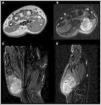

Synovial sarcoma (SS) is a rare malignant neoplasm of the soft tissue adjacent to joints. It is the most commonly diagnosed non-rhabdomyosarcoma soft-tissue sarcoma (STS) in childhood (30%). Its most frequent location is the knee and ankle, and it is the most common STS to affect the foot. Unlike other STS, it has slow growth and an earlier age at diagnosis (adolescents and young adults), which is why many cases are initially misdiagnosed as benign processes. Magnetic resonance imaging (MRI) is key due to its characterisation capabilities as SS shares features with other STS. Definitive diagnosis is achieved through a pathological study that shows the pathognomonic translocation t(x;18)(p11;q11) with the fluorescence in situ hybridisation (FISH) technique. The objective of this article is to highlight the key characteristics that are useful for diagnosing SS, fundamentally through the use of radiological imaging techniques, as well as nuclear medicine and pathological studies, illustrated with cases diagnosed in our centre.

El sarcoma sinovial (SS) es una neoplasia maligna infrecuente del tejido blando adyacente a las articulaciones, siendo el sarcoma de tejidos blandos (STB) de tipo «no rabdomiosarcoma», más diagnosticado en la infancia (30%). Su localización más frecuente es la rodilla y tobillo, representando el STB más común del pie. A diferencia de otros STB, presenta un crecimiento lento y una edad más temprana al diagnóstico (adolescentes y adultos jóvenes), por lo que muchos casos son inicialmente diagnosticados como procesos benignos de forma errónea. La resonancia magnética (RM) es clave para su caracterización, si bien comparte características con otros STB. El diagnóstico definitivo es anatomopatológico, que evidencia la translocación patognomónica t(x;18)(p11;q11) con técnica de hibridación fluorescente in situ (FISH). El objetivo de este artículo, ilustrado con casos diagnosticados en nuestro centro, es resaltar las características claves para el enfoque diagnóstico del SS, fundamentalmente mediante el uso de técnicas de imagen radiológicas, así como estudios de medicina nuclear y anatomopatológicos.